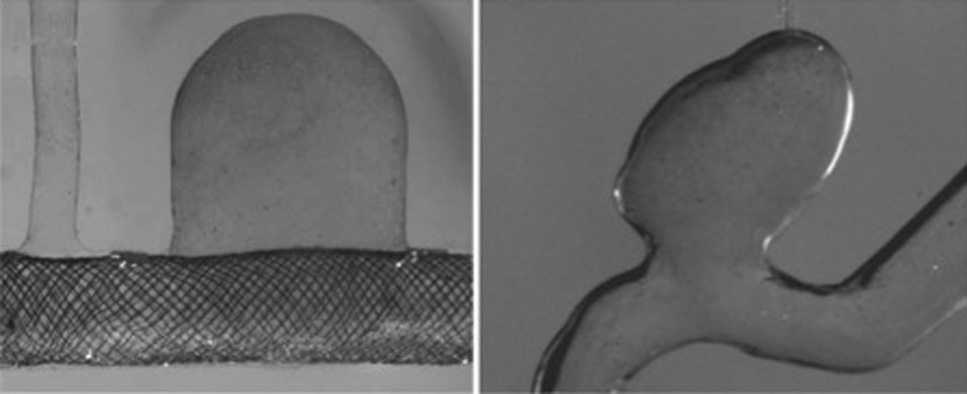

本研究使用了两个侧壁动脉瘤的透明聚氨酯模型。图3(a)所示的理想化模型在SolidWorks(Dassault Systems,马萨诸塞州沃尔瑟姆)中设计,并按照参考文献[26]中的描述进行制造。图3(b)所示的解剖模型由患者特异性计算机断层扫描图像重建,并按照参考文献[27–30]中的描述进行制造。